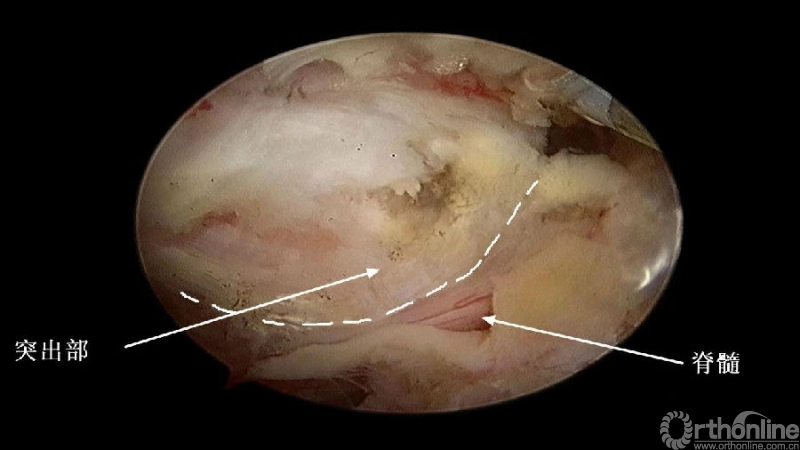

颈椎内镜下单侧入路双侧减压(ULBD)中,减压的难点还是在于识别棘突与椎板的移行部位及对侧结构的显露。

入院查体患者四肢肌张力高,双侧hoffman阳性。CT及MRI检查提示C4/5左侧关节突内缘有一巨大骨块(15mm*16mm),相应节段椎管严重狭窄。椎管内骨块的前端还有一游离骨块。

3.从游离骨块的背侧开始,用磨钻将骨块打薄,然后将骨块的底面与脊髓表面仔细分离,将游离骨块摘除;

4.进一步加深移除骨赘的残余部分,直到显露出对侧的神经根及关节突关节的内壁;